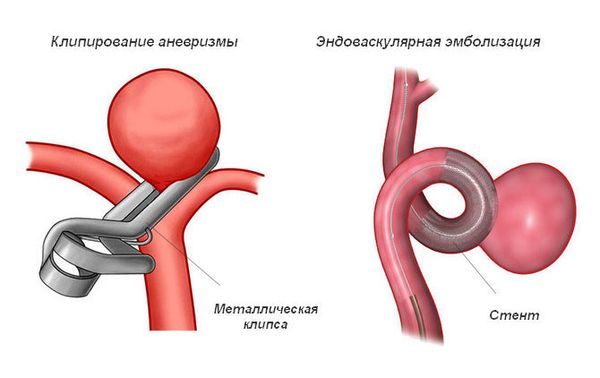

Снимки и иллюстрации микроаневризм сосудов головного мозга